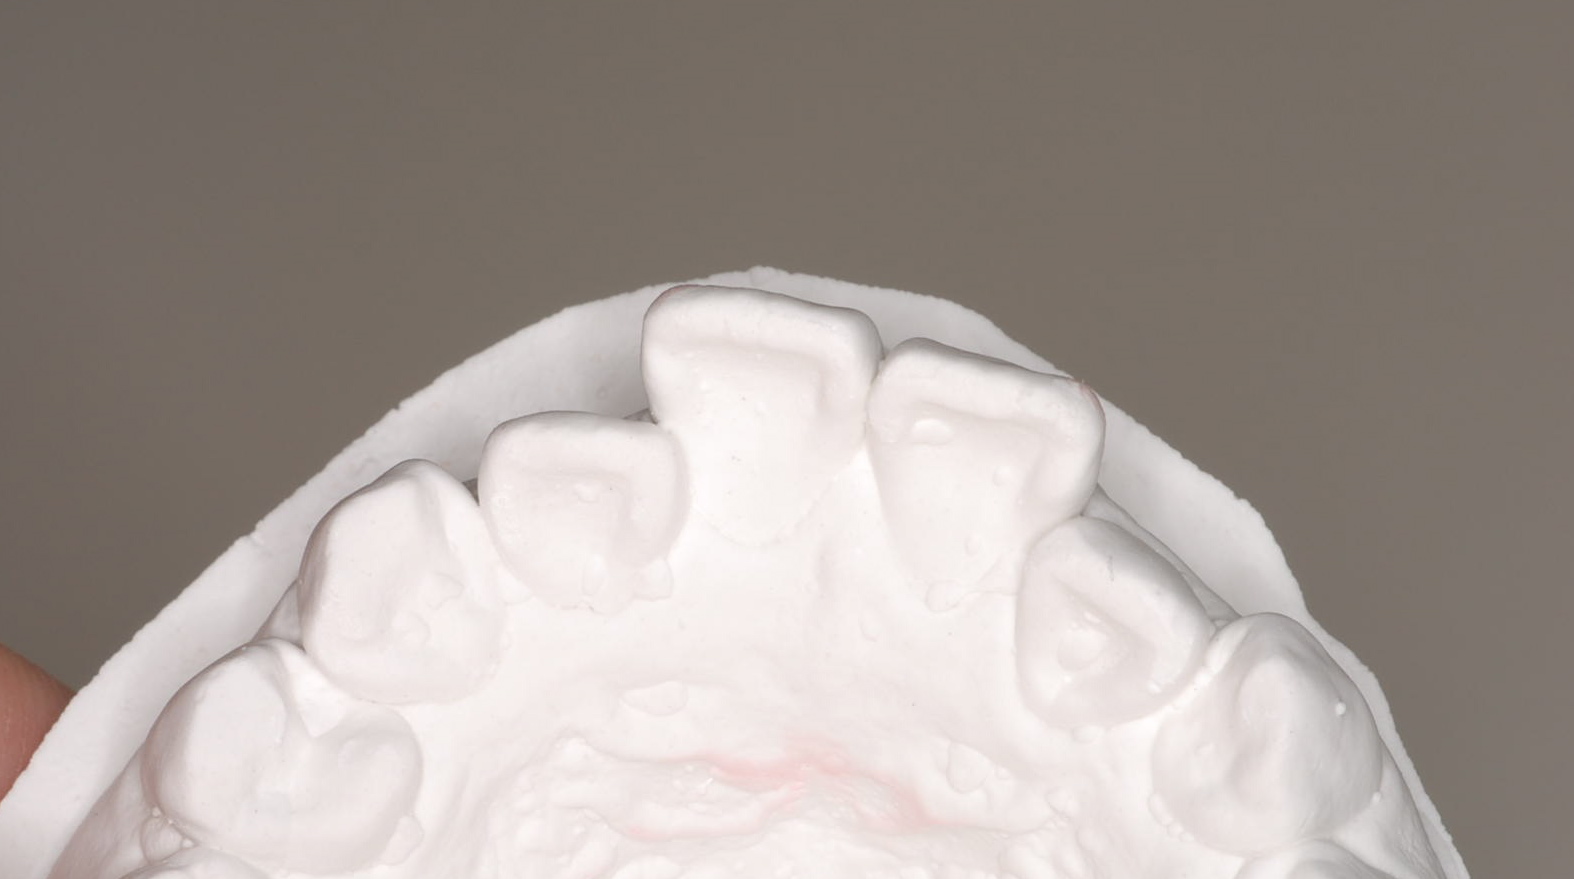

セットアップを作製。この時点でも患者さんと話し合い、TEK(仮歯)を作り、

患者さんが納得いく形を決めました。

セットアップ